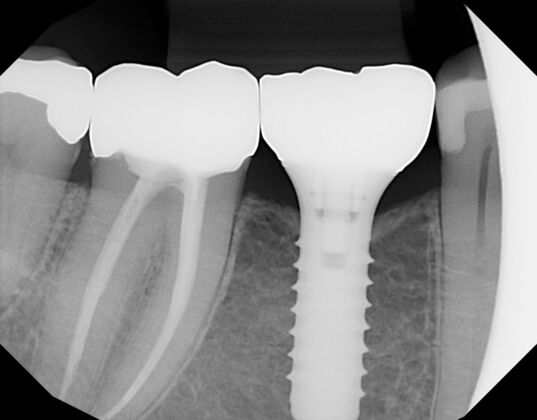

Implant with Zirconium crown and Emax crown